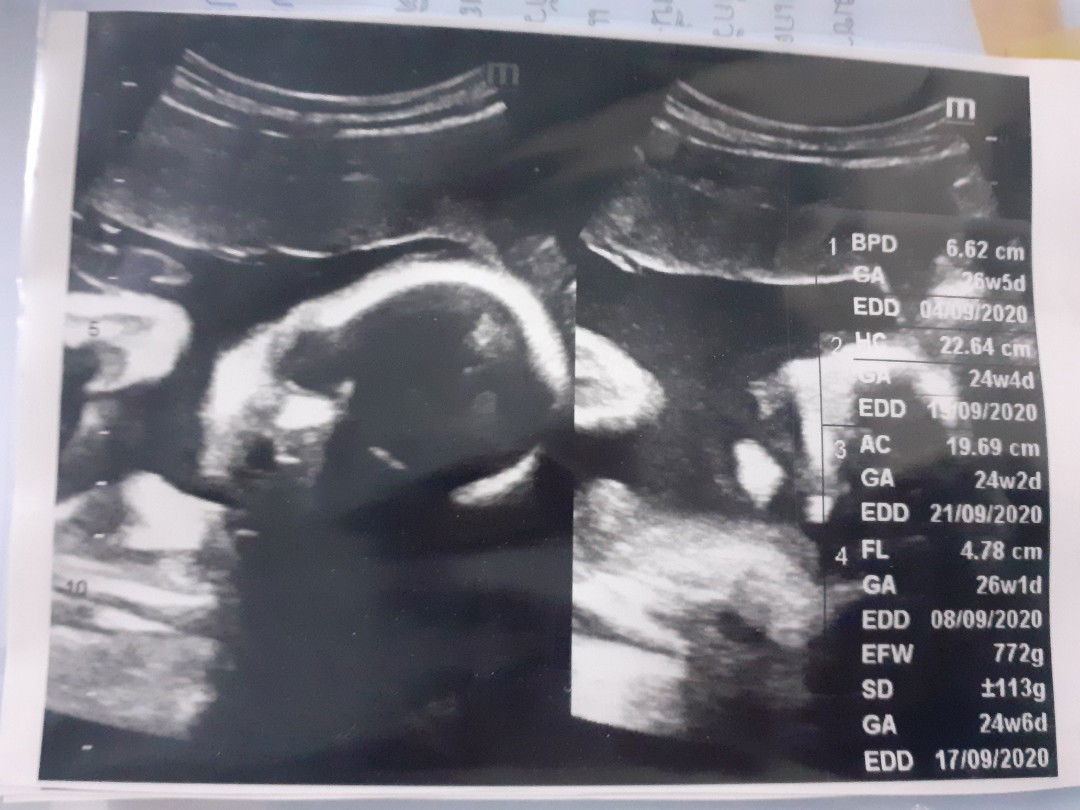

ครรภ์

เห็นหน้าลูกๆกันรึยังแม่ๆ #หนูหลับตลอดเลย???

#6เดือนแล้ว แม่ๆท่านอื่นว่าไง อวดท้องกันหน่อย ท้อง3แล้วจร้าา